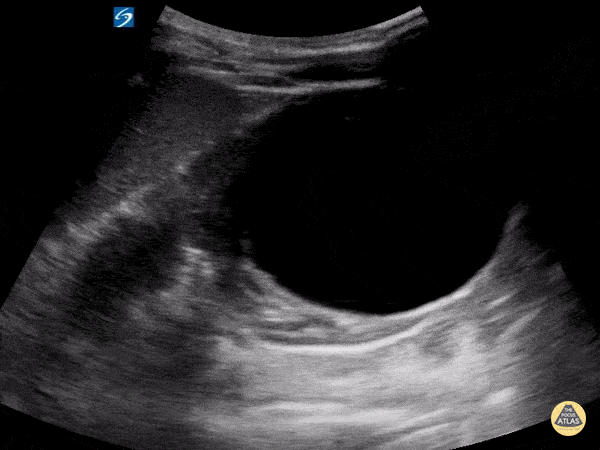

Peds-Genitourinary - Renal Cyst

Healthy 7 year old male modeling for educational US scanning. Found to have large simple large renal cyst. Contributor: Matthew Moake, MD PhD